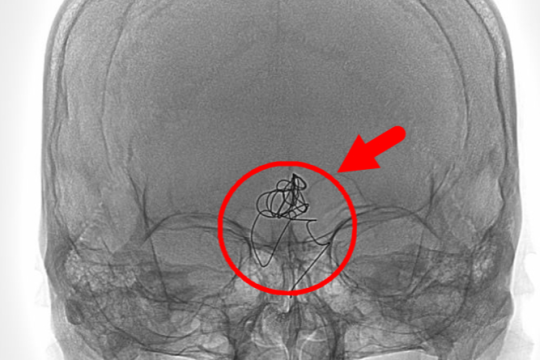

据统计,浙大一院近年来年均实施大器官移植手术 1300 余台,涵盖肝移植、肾移植、心脏移植、小肠移植、肺移植等,并不断挑战肝肾联合移植、心肺联合移植等高难度复杂移植手术,屡次突破器官移植「无人区」。浙大一院率先把达芬奇机器人应用于肝胆胰外科、泌尿外科、肾脏病中心、普胸外科、妇科、结直肠外科、胃肠外科、心脏大血管外科等科室的手术,为曾经「无法手术」的无数患者带来生命奇迹。